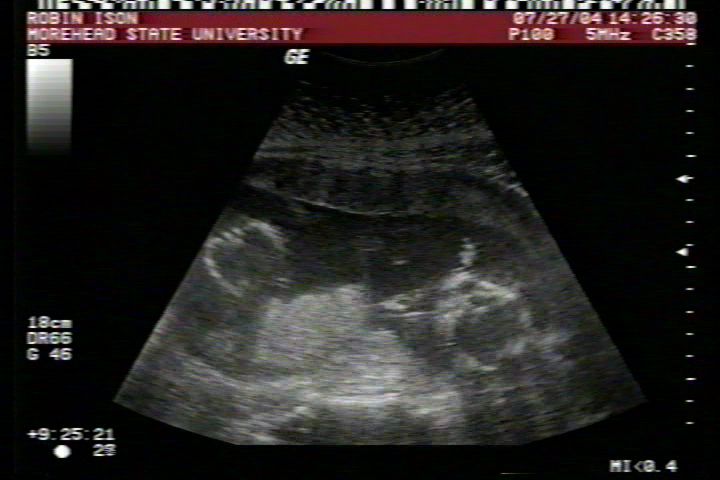

Pictures from Ultrasound at 17 weeks.